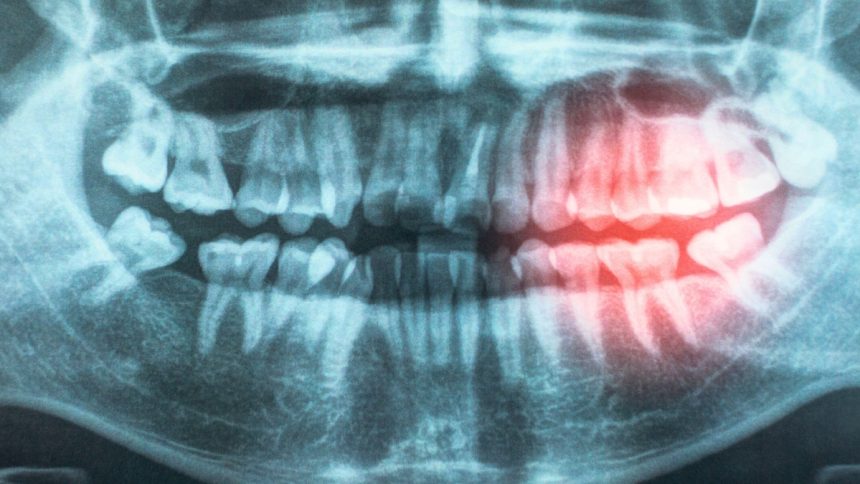

The researchers explored potential reasons for this association, suggesting that bacteria entering the body through damaged gums could lead to chronic inflammation, contributing to heart disease. Pediatric cardiologist Andrew Tran emphasizes the connection between oral and heart health, stating that gum disease and poor oral hygiene can allow bacteria to enter the bloodstream, damaging blood vessels and increasing the risk of heart disease.

While many risk factors such as smoking, aging, and obesity increase the likelihood of both gum disease and atherosclerotic cardiovascular disease (ASCVD), emerging evidence suggests an independent association between the two conditions. ASCVD remains the leading global cause of death, making it crucial to investigate how improving oral hygiene could potentially prevent heart disease.